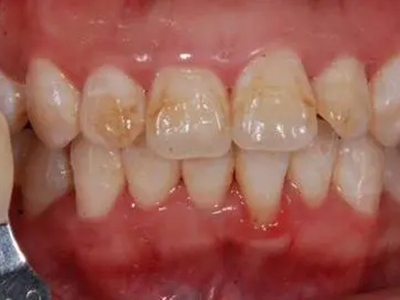

牙釉质发育不全牙表面上有坑图

牙釉质发育不全发展到严重时,导致牙釉质表面缺损,表现为带状、窝状的褐色凹坑,容易积存食物残渣诱发龋齿,表现为牙齿边上出现深褐色小洞。